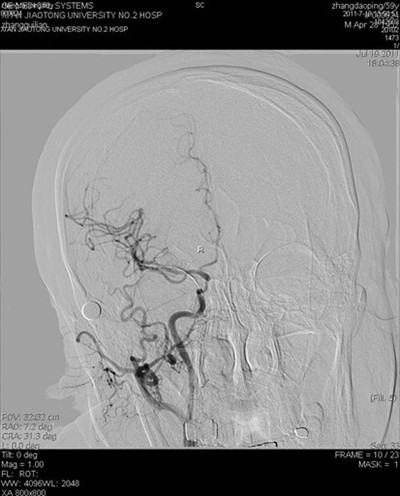

(图3)术后病灶血管远端颅内血管显影良好

患者张某,59岁,以左侧肢体活动不灵14天入院,14天前患者突然出现左侧肢体无力,活动受限,并言语含糊,曾于外院就诊,脑CT及MR提示脑梗死,治疗后效果不明显,遂来我院。既往有高血压史数年,长期间断服降压药。入院查体:血压180/100mmHg,左侧口角低,左侧鼻唇沟浅,左侧上下肢瘫痪,肌力III+,左侧肢体共济运动差,左侧巴氏征阳性。余查体未见明显异常。辅助检查:空腹血糖9.8mmol/l。根据患者病史、外院影像学检查,考虑诊断为1.脑梗死(分水岭区);2.高血压病(III级,极高危);3.糖尿病(2型)。为了进一步明确患者脑梗死病因,确定下一步治疗方案,在家属签字同意下,于2011年7月19日进行了全脑血管造影术,术中发现右侧颈内动脉开口处闭塞,但远端血流通过后交通依稀可见,经过我科介入小组缜密讨论,拟给患者行闭塞血管再通手术,经过2小时的紧张手术,取得了很好的手术效果,患者安返病房(见图)。本次手术的成功,是继6月我们对急性闭塞血管进行取栓,我院神经介入工作的又一次突破,在血管闭塞后14天再通,在国内外少见报道,这将快速推动神经介入工作的进一步发展。